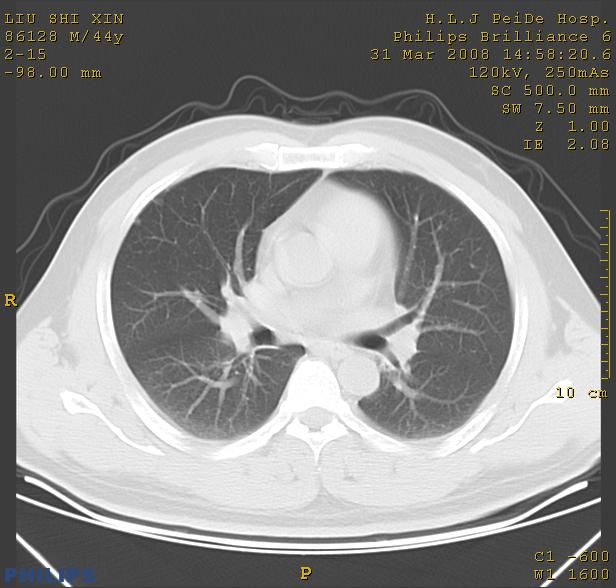

标题: CT13096:请分析胸膜下结节的影像基础是什么 有病理结果 [打印本页]

标题: CT13096:请分析胸膜下结节的影像基础是什么 有病理结果

瘢痕挛缩,胸膜牵拉,血管纠集扭曲,上叶前段支气管显示欠清,周围散在斑片影,以纵隔旁肺癌可能性大。请穿刺检查。

中心型肺癌并阻塞性肺炎及肺内转移

中心型肺癌并阻塞性肺炎、两肺及胸膜多发转移。

结节灶与血管末梢相通象转移灶;小三角状尖部有纤维索是胸膜拉扯征;纵隔旁大片实性影有点状钙化;周围有名显纤维瘢痕征可考虑瘢痕癌

本病例有病理结果是,鳞状上皮癌,胸膜下结节影病现诊断的肿大淋巴结,谢谢大家分析,请问胸膜下结节是肿大淋巴结怎么解释